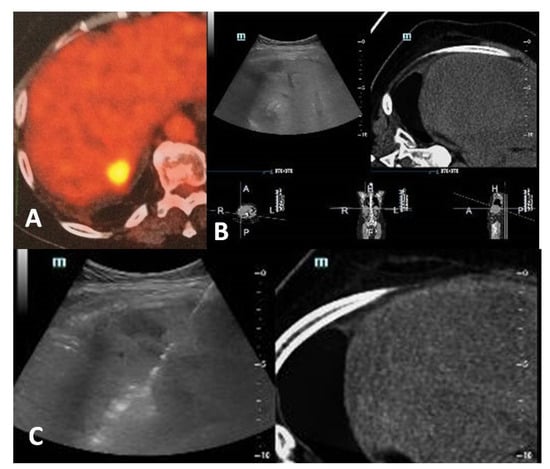

- Cornelis, F.; Sotirchos, V.; Violari, E.; Sofocleous, C.T.; Schoder, H.; Durack, J.C.; Siegelbaum, R.H.; Maybody, M.; Humm, J.; Solomon, S.B. 18F-FDG PET/CT is an immediate imaging biomarker of treatment success after liver metastasis ablation. J. Nucl. Med. 2016, 57, 1052–1057. [Google Scholar] [CrossRef]

- Mauri, G.; Gennaro, N.; De Beni, S.; Ierace, T.; Goldberg, S.N.; Rodari, M.; Solbiati, L.A. Real-time US-(18)FDG-PET/CT image fusion for guidance of thermal ablation of (18)FDG-PET-positive liver metastases: The added value of contrast enhancement. Cardiovasc. Intervent. Radiol. 2019, 42, 60–68. [Google Scholar] [CrossRef]

- Ryan, E.R.; Sofocleous, C.T.; Schöder, H.; Carrasquillo, J.A.; Nehmeh, S.; Larson, S.M.; Thornton, R.; Siegelbaum, R.H.; Erinjeri, J.P.; Solomon, S.B. Split-dose technique for FDG PET/CT-guided percutaneous ablation: A method to facilitate lesion targeting and to provide immediate assessment of treatment effectiveness. Radiology 2013, 268, 288–295. [Google Scholar] [CrossRef]

- Cornelis, F.H.; Petre, E.N.; Vakiani, E.; Klimstra, D.; Durack, J.C.; Gonen, M.; Osborne, J.; Solomon, S.B.; Sofocleous, C.T. Immediate postablation 18F-FDG injection and corresponding SUV are surrogate biomarkers of local tumor progression after thermal ablation of colorectal carcinoma liver metastases. J. Nucl. Med. 2018, 59, 1360–1365. [Google Scholar] [CrossRef]